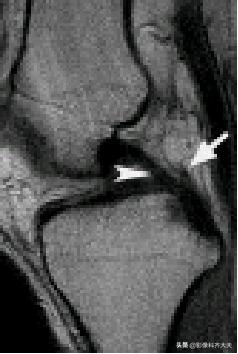

容易误诊为半月板损伤的正常解剖结构

腘肌腱腱鞘: